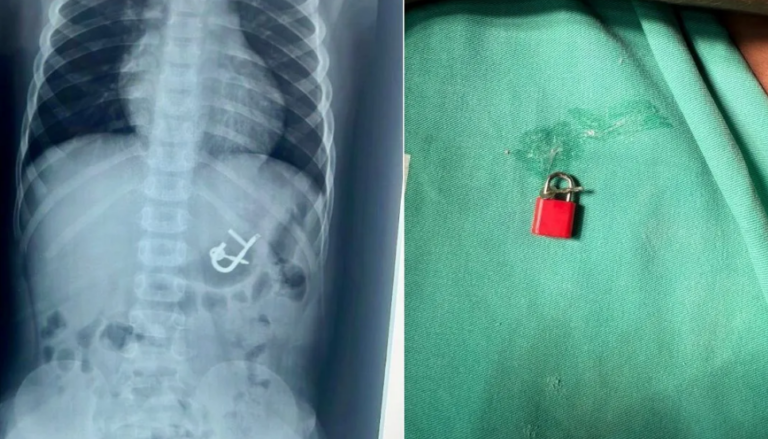

Uma criança de quatro anos passou por uma endoscopia digestiva para a remoção de um cadeado com as chaves no Hospital Regional Inácio de Sá, em Salgueiro, no Sertão de Pernambuco, após engolir o objeto durante uma brincadeira.

Em entrevista à CNN nesta quarta-feira (15), a diretora médica Thaís Sampaio explicou como realizou o procedimento no garoto, que, tentando retirar as chaves do cadeado, perdeu o equilíbrio e acabou caindo e engolindo o objeto, de aproximadamente 5 cm.

“Foi um caso curioso, pois o objeto engolido era grande e poderia causar sérios danos, como uma obstrução intestinal”, contou a médica. “Graças ao novo aparelho de endoscopia, que recentemente foi disponibilizado pela Secretaria de Saúde, conseguimos realizar o procedimento”, complementou. Segundo a doutora, antes, os pacientes que precisavam da remoção de objetos engolidos eram submetidos a uma cirurgia ou precisavam ser encaminhados para o Recife, a 500 quilômetros de distância, para realizar o procedimento.

“A retirada foi tranquila. Assim que entramos, já avistamos o cadeado no estômago, como mostrava o Raio-x. Usamos uma pinça especializada e uma cestinha, que chamamos de basket. Você tem uma pinça especializada para isso. E conseguimos retirar por via oral, sem nenhuma lesão. Não houve danos no estômago nem no esôfago, e todo o procedimento transcorreu na maior tranquilidade”, explicou a doutora Thaís Sampaio.